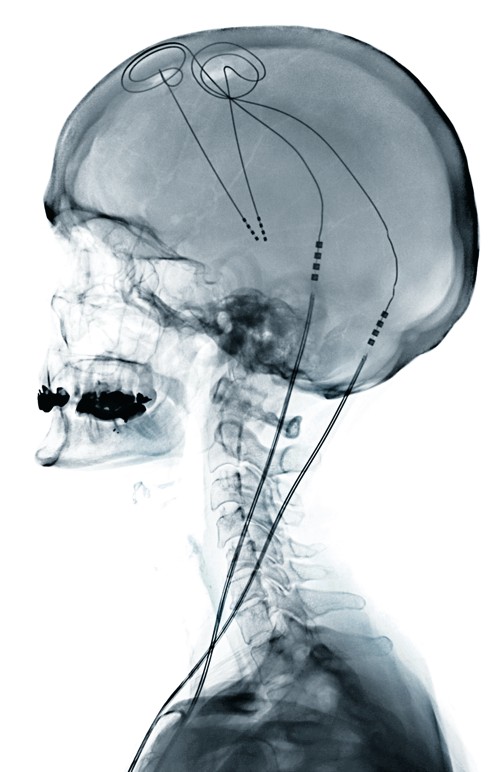

The medical treatment of parkinson disease from james parkinson to george cotzias. La thérapie de stimulation cérébrale profonde (scp) pour la maladie de parkinson utilise un appareil médical implanté par voie chirurgicale, semblable à un stimulateur cardiaque, pour stimuler électriquement des zones bien ciblées du cerveau. La stimulation cérébrale profonde (abrégée scp dans la suite de l'article) est une étude récente a montré que chez 45 patients atteints de la maladie de parkinson soumis à une scp du noyau subthalamique (l'une des cibles cérébrales les plus courantes de la maladie de parkinson), il y avait. La stimulation cérébrale profonde est un traitement adapté à chaque personne. Une stimulation plus fine et plus fiable. Le patient présente alors un stade. Dans le cadre du plan maladies neurodégénératives, l'association france parkinson participe à un groupe de travail sur le sujet de la stimulation cérébrale profonde. Durant la stimulation cérébrale, des électrodes ont été placées dans certaines zones du cerveau pour corriger et contrôler les tremblements générés par la maladie de parkinson.

Durant la stimulation cérébrale, des électrodes ont été placées dans certaines zones du cerveau pour corriger et contrôler les tremblements générés par la maladie de parkinson.

En effet, la neurostimulation (ou stimulation cérébrale profonde, scp) ne sera proposée qu'à des patients parkinsoniens (présentant une maladie de parkinson idiopathique) motivés et Vous devez être opéré(e) pour avoir une stimulation cérébrale profonde dans le cadre de mouvements anormaux invalidants, comme la maladie de parkinson, le tremblement essentiel, une dystonie généralisée ou. But in many cases it has given people with the condition better control. En fait, des travaux publiés dans le new england journal of medecine montrent que ce. Elle touche 150 000 personnes en france et près de. Parkinson est une maladie neurologique progressive qui se manifeste notamment par des tremblements. La stimulation cérébrale profonde (scp) à haute fréquence est une thérapeutique efficace pour le traitement symptomatique de nombreuses pathologies du mouvement telles que la maladie de parkinson (mp), le tremblement essentiel (te) et les dystonies. La stimulation cérébrale profonde à haute fréquence, thérapeutique efficace pour le traitement symptomatique de la maladie de parkinson, a alors été proposée à ce patient. La stimulation cérébrale profonde qui consiste envoyer une stimulation électrique à une région spécifique du cerveau grâce une électrode reliée à un neurostimulateur. L'intervention permet d'obtenir des résultats. Dans un essai de faisabilité à court terme, deux patients atteints de la maladie de parkinson ont reçu un dispositif de stimulation cérébrale profonde, entièrement implanté et adapté au niveau de leur cortex moteur primaire. C'est que suggère pour la première fois dans « neurology » une petite étude américaine randomisée chez 28 patients à un stade très précoce. Your device can't be programmed until the swelling in your brain goes down.